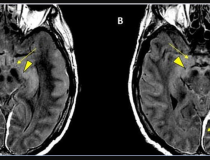

This photo gallery shows the variety of radiological presentations of COVID-19 (SARS-CoV-2) in medical imaging, including computed tomography (CT), radiograph X-rays, ultrasound, echocardiograms and magnetic resonance imaging (MRI). The radiology images show examples of typical COVID pneumonia in the lungs and the numerous complications the virus causes in the body in multiple organs, including the brain, kidneys, heart, abdomen and vascular system.

Ultrasound, especially hand-held ultrasound imaging devices, have become a primary imaging modality for novel coronavirus because of the ease to bag the device and sterilize it after use. CT and mobile X-ray systems are also used as front-line imaging systems for COVID-positive or suspected COVID patients.